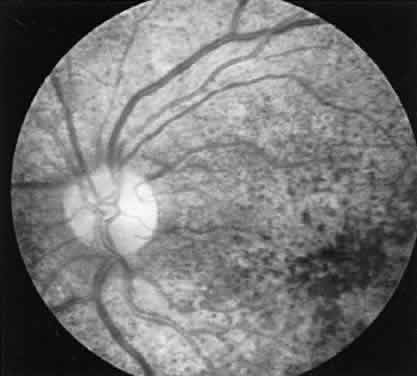

CASE 1 (FIG. 8). A 49-year-old female had poor night vision from childhood and recent difficulty going down stairs. There was no family history of any similar disorder. Vision 20/25 OD, 20/20 OS. Both fundi showed slightly pale discs, attenuated arterioles, a motheaten appearance of the retina, and peripheral bone spicules. Visual fields were 10 degrees on a Goldmann perimeter (III-4E). The ERG was extinguished.

Fig. 8. Case I. See text for details.

This is a classic case of retinitis pigmentosa with the ERG providing confirmatory evidence to the typical history, clinical picture, and visual fields.